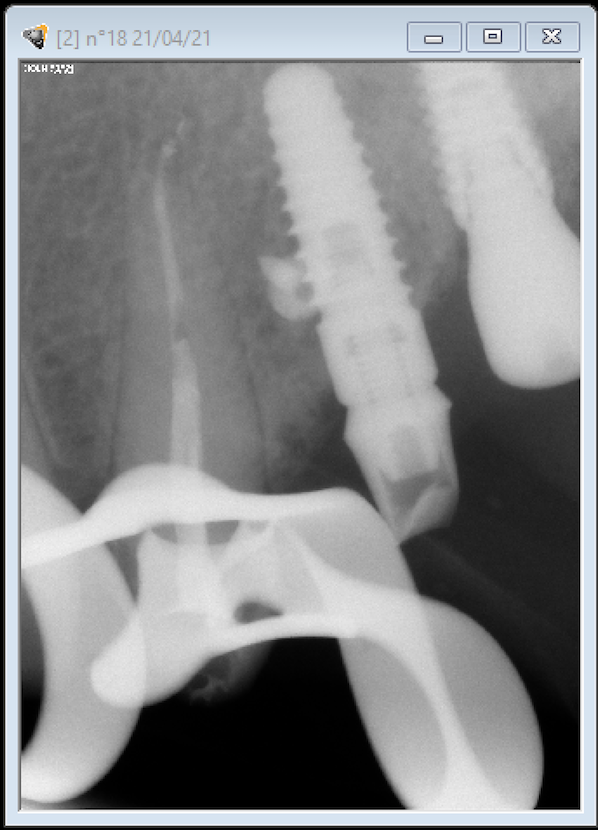

Buenos días. OS adjunto las fotografías de las periapicales de un implante colocado en la pieza 24, para que me ayudéis con la identificación.

Se trata de un implante BTK de 4 mm de diámetro.

La plataforma que tiene es de la conexión interna tipo Zimmer de 3.5 mm. Métrica de tornillo 1.8 mm. Destornillador 1.2 mm hexagonal.